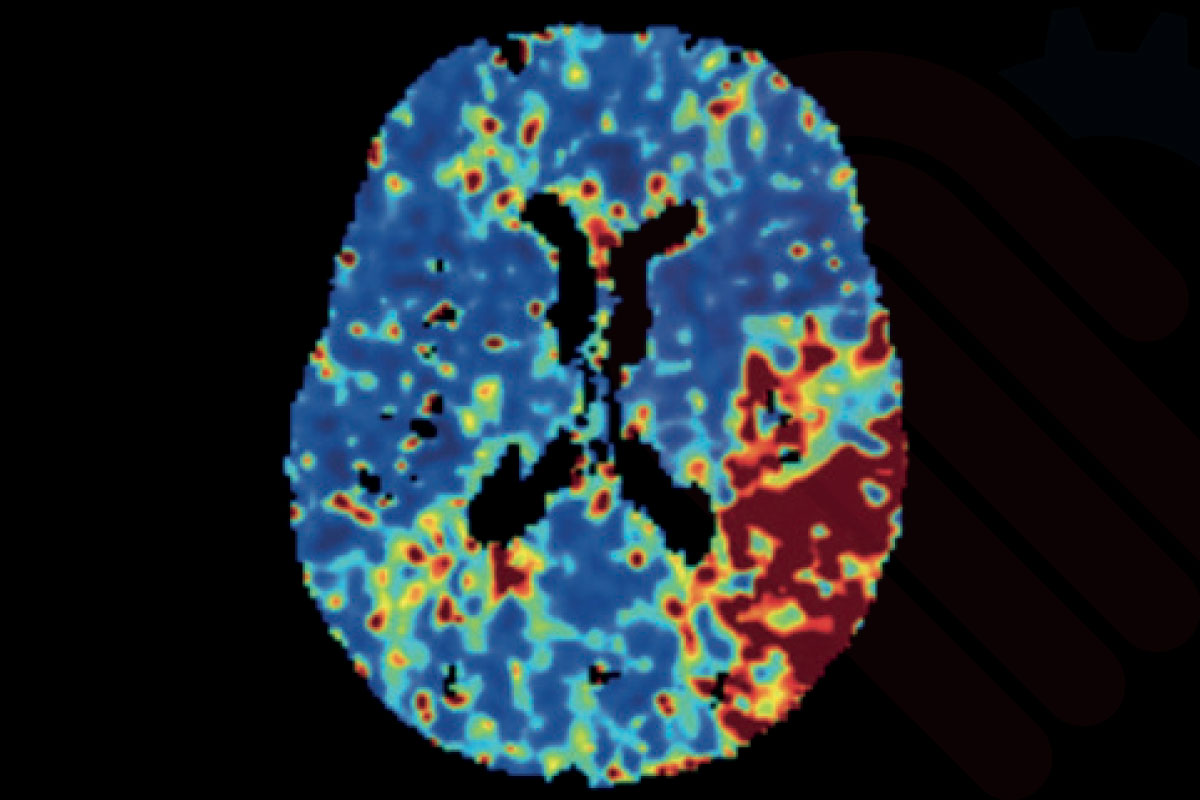

Cercare Medical Neurosuite Stroke yazılımının Gelişmiş SVD (Singular Value Decomposition) tabanlı perfüzyon analizleri, standart versiyona kıyasla daha ileri algoritmalar kullanarak doku perfüzyonunu hassas şekilde haritalandırır. Bu modül, beyin kan akımı (CBF), beyin kan hacmi (CBV), ortalama geçiş zamanı (MTT), zaman-gecikmesi (Tmax), maksimum yoğunluk projeksiyonu (MaxIP) ve tepe zamanı (TTP) parametrelerini yüksek doğrulukla hesaplar.

Gelişmiş SVD analizleri, özellikle iskemik penumbra (kurtarılabilir doku) ile infarkt çekirdeği (geri dönüşsüz doku) arasındaki ayrımı daha kesin yapabilmek için tasarlanmıştır. Klinik çalışmalar, bu yaklaşımın tedavi penceresinin uzatılmasına katkıda bulunduğunu ve uygun hasta seçimini %15–20 oranında daha isabetli hale getirdiğini göstermektedir*.

Ayrıca gelişmiş algoritmalar, standart SVD’de görülebilen gürültü ve artefaktları azaltarak hem CT hem de MR perfüzyon verilerinde daha temiz ve güvenilir haritalar üretir. Bu, tromboliz ve trombektomi gibi kritik tedavi kararlarının daha güvenle alınmasını sağlar.

Vasküler Model Tabanlı Perfüzyon Haritaları

Cercare Medical Neurosuite Stroke yazılımının gelişmiş paketinde yer alan vasküler model tabanlı perfüzyon haritaları, beynin damar yapısını hesaba katan sofistike algoritmalarla çalışır. Klasik SVD tabanlı yöntemlerin ötesine geçerek, kan akış dinamiklerini biyofiziksel modellerle birleştirir. Böylece beyin kan akımı (CBF), beyin kan hacmi (CBV), ortalama geçiş zamanı (MTT) ve gecikme parametresi (Tmax) gibi temel ölçümler, damar ağı simülasyonları üzerinden yeniden hesaplanarak daha yüksek doğruluk elde edilir.

Bu yaklaşım, özellikle yan akım dolaşımı (collateral circulation) bulunan inme hastalarında kritik öneme sahiptir. Klinik araştırmalar, vasküler model tabanlı analizlerin çekirdek infarkt alanı ile penumbra bölgesini ayırmada %15’e varan ek doğruluk sağladığını ve yanlış negatif oranını anlamlı şekilde azalttığını göstermektedir*. Böylece tedaviye uygun hasta seçiminde güvenilirlik artar, tedavi penceresi daha sağlıklı değerlendirilir.